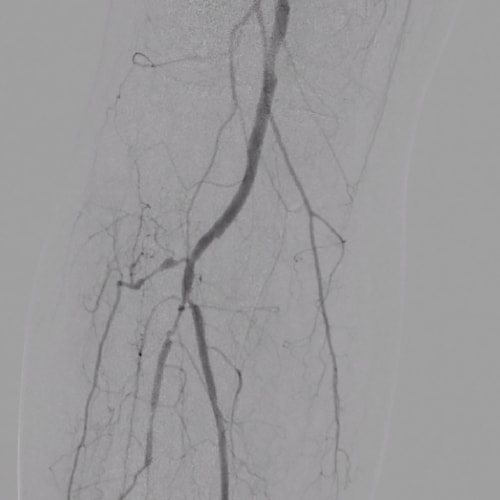

DSA

The DSA and roadmap functions make it suitable for intravascular procedures.